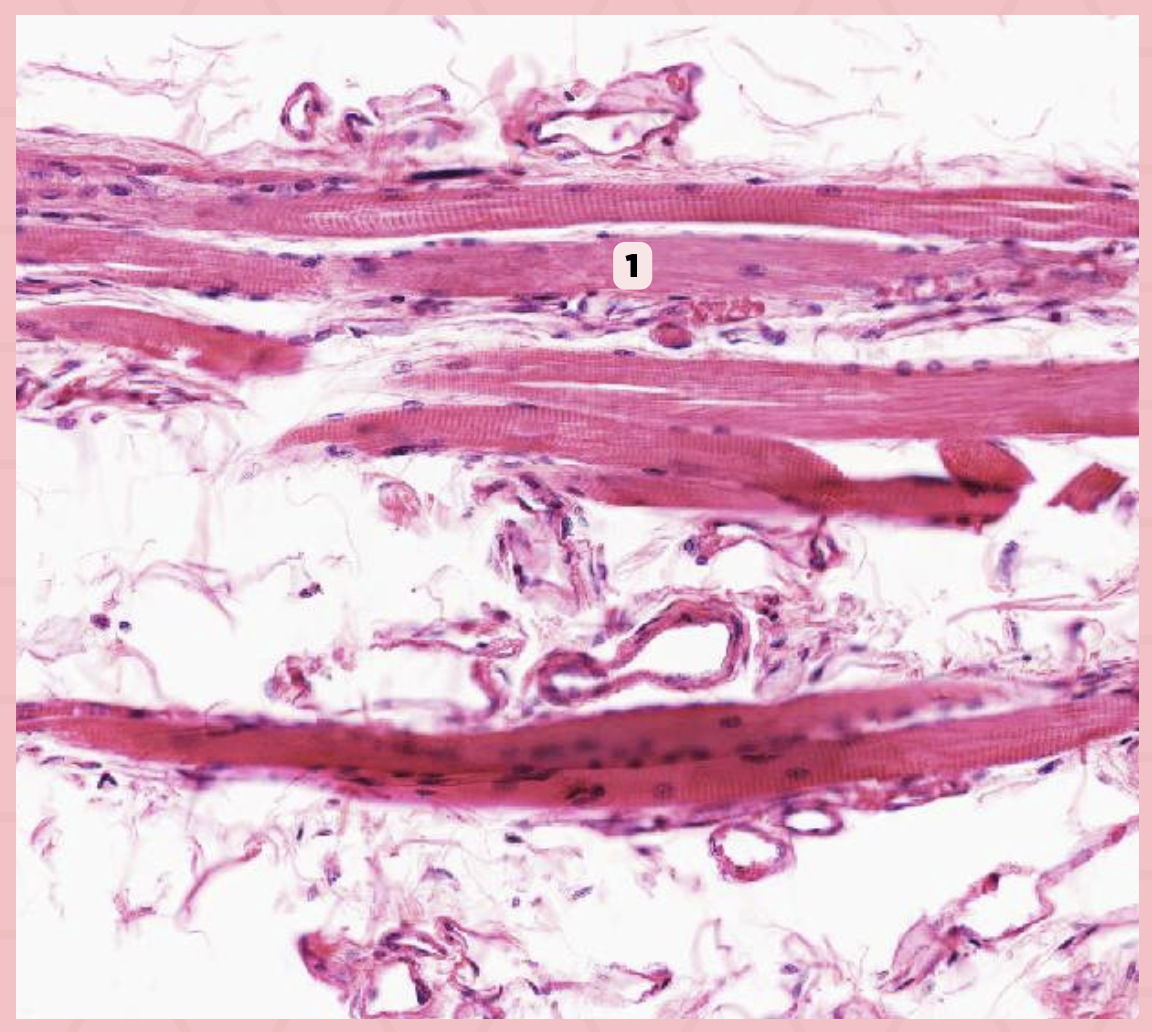

Skeletal Muscle Fibers

Identify the structure labeled as 1.